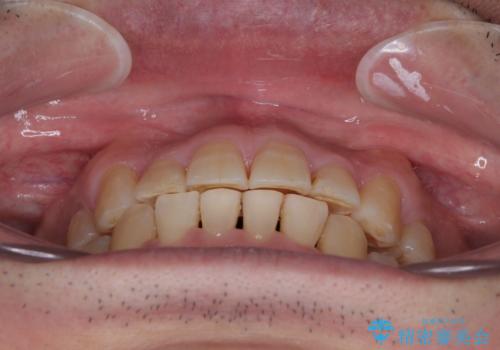

まずは奥歯の痛みを改善し、その後矯正治療を行い、最後にオールセラミックブリッジによる補綴治療を行うこととしました。

むし歯をきっかけに矯正治療を行うこととなりましたが、学生の頃から気になっていた歯列を改善することができ、患者様には大変満足していただけました。